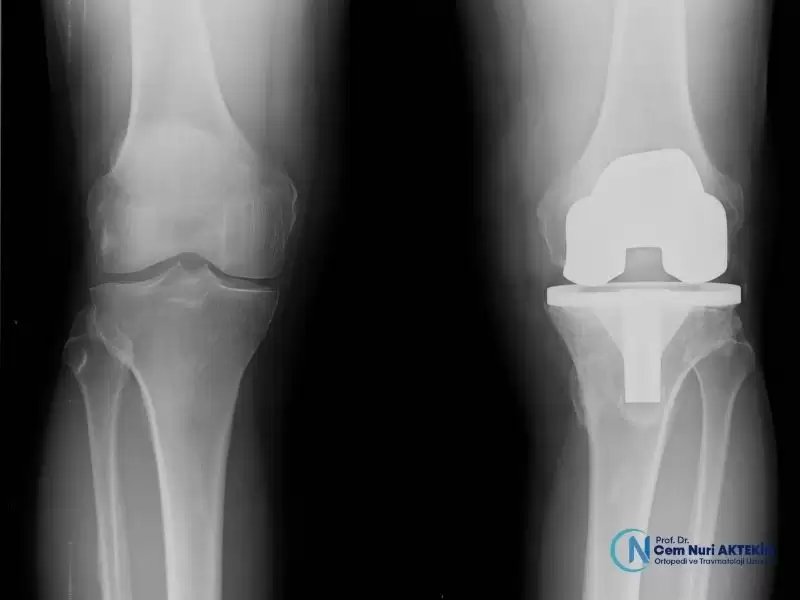

Menisküs Nakli, Total Diz Protezi, Diz Ağrısı, Yarım Diz Protezi, Dizde Kireçlenme, Menisküs tedavileri için cerrahi ve cerrahi olmayan, ihtiyacınıza göre kişiselleştirilmiş tedavi planları ile hareket özgürlüğünüzü yeniden kazanın.

• Protez Cerrahisi